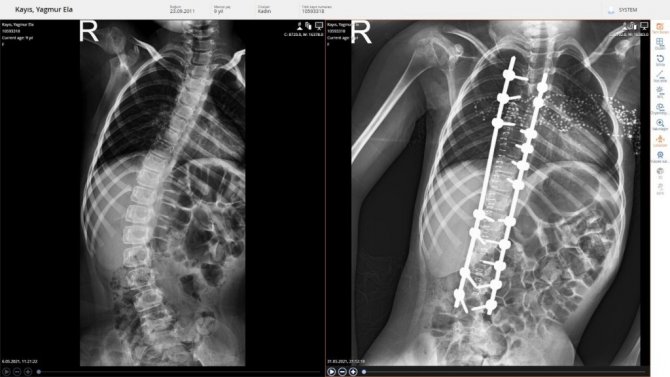

Doğuştan skolyoz eğriliği olan 9 yaşındaki Yağmur Ela, Sivas'ta yapılan ameliyatla sağlığına kavuştu.

Sivas'ta 9 yaşındaki Yağmur Ela, solunum sıkıntısı çekmeye başlayınca ailesi tedavi ettirmek için arayışa girdi. Sivas Cumhuriyet Üniversitesi Araştırma ve Uygulama Hastanesi Beyin Cerrahi Kliniğine gelen Yağmur Ela, yapılan muayene ve tetkikleri sonucunda ameliyat edilmeye karar verildi. Ameliyatı gerçekleştiren Beyin ve Sinir Cerrahisi Ana Bilim Dalı Başkanı Ünal Özüm tarafından ameliyatı gerçekleştirilen Yağmur Ela'nın sağlığına kavuştu.

Prof. Dr. Ünal Özüm, sadece bazı büyük merkezlerde yapılan bu tür ameliyatların Sivas Cumhuriyet Üniversitesi Hastanesinde de yapılmaya başlandığını belirterek, "Çocuğumuz 8 yaşında, 9'a girmek üzere. Omurgasında ciddi eğrilik, halk arasında kamburluk ya da kifoskolyoz, omurgada eğrilik diye tanımlanan hastalığı var. Bu hastalıkta aslında ameliyatları 13-14 yaşında yapmak lazım; ama omurgası çok eğri olduğu için çocuğun nefes almasında ciddi sıkıntı var. Akciğerde sönme, oturma pozisyonunda çok fazla bozukluk olduğundan erken ameliyat olmasına karar verdik " dedi.

Yağmur Ela'nın annesi Kudret Güleç ise çocuğunun doğuştan skolyoz hastası olduğunu son aylarda nefes darlığı da başladığını söyledi. Yağmur Ela'nın her geçen gün sıkıntılarının arttığını buna da çare için Türkiye'nin pek çok yerinde tedavi imkânı aradıklarını belirten Güleç, "Gittiğimiz hastanelerde "yaşı küçük olduğu için yapamayız, edemeyiz" dediler. "Ameliyat masasında kalır" diye çok söyleyenler oldu. En son da sol tarafında kemik oluştu. Sol tarafındaki kemik, akciğere baskı yaptığı ve akciğeri parçalayıp ölüm riski olduğu söylenildi. MR çekildik ve buraya geldik. Bir de Ünal Hocamıza danışalım dedik. İşinde bir numaralı doktor olduğu için ve güvencemiz de kendisine sonsuz olması itibariyle başvuru yaptığımızda bizden ve MR, röntgenler ve tomografiler istendi. Ameliyatına karar verildi. Çok şükür sağ salim kucağımıza aldık" diye konuştu.